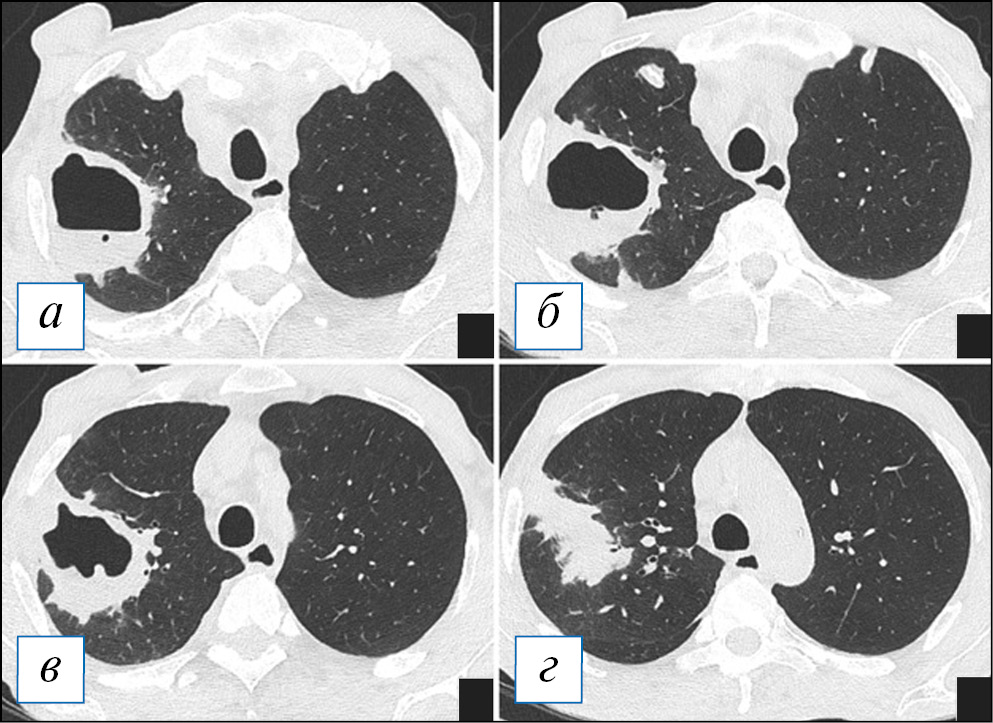

По данным компьютерной томографии (КТ) у пациентов с очаговой пневмонией обнаруживают небольшие перибронхиальные очаги, обычно солидного типа или с нечеткими контурами за счет ободка «матового стекла», при бронхиолите — мелкие очажки в виде симптома «дерева с набухшими почками», при этом прилежащие стенки бронхов могут быть утолщены и уплотнены за счет воспалительного процесса. Возможно слияние очагов, которое не принимает характера обширной инфильтрации. При пневмонии контуры очагов менее четкие из-за преобладания экссудативного воспалительного компонента, что отличает ее от бронхиолита [38]. Важным симптомом бронхогенного процесса можно рассматривать наличие патологического содержимого в просвете бронхов, что представлено слизистым или гнойным содержимым (рис. 1). На традиционных рентгенограммах изменения из-за малого размера могут быть вовсе не заметны или представлять собой мелкие очаги/ограниченную диссеминацию; отмечается локальное усиление/обогащение легочного рисунка, преобладающее в какой-то одной доли легкого.

Рис. 1. Компьютерная томография органов грудной клетки в аксиальной проекции (а–г). Двусторонняя сливная бронхопневмония и бронхиолит у пациента с наличием в мокроте S. pneumoniae и S. aureus в значимых титрах. С обеих сторон, больше в нижних долях, на фоне обтурации просветов крупных бронхов патологическим содержимым (стрелки) имеются перибронхиальные разнокалиберные очаги, в том числе по типу симптома «дерева с набухшими почками» (рамка). В верхних отделах данные очаги сливаются в инфильтраты. [Изображения из архива авторов]. / Fig. 1. Chest CT, axial projection (а–г). Bilateral bronchopneumonia and bronchiolitis (with the etiology of S. pneumoniae and S. aureus confirmed by a sputum test). On both sides, more in the lower lobes against the background of bronchial sputum obturation (arrows), there are peribronchial nodules of various sizes, including a “tree in bud” sign (frame). In the upper lungs areas the nodules formed infiltrates. [Images from the authors’ archive].